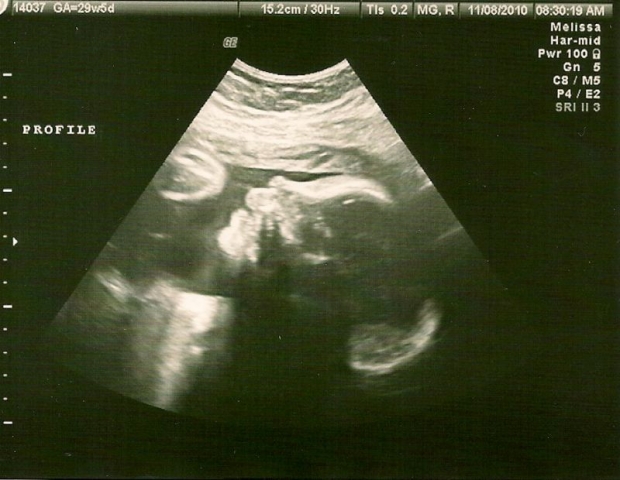

УЗИ: 29 неделя беременности

Обследование позволяет определить массу тела плода. На данном этапе считается, что его вес составляет примерно половину от того, что он будет иметь после рождения. Костный мозг активно производит эритроциты, а все кости малыша уже полностью развиты.